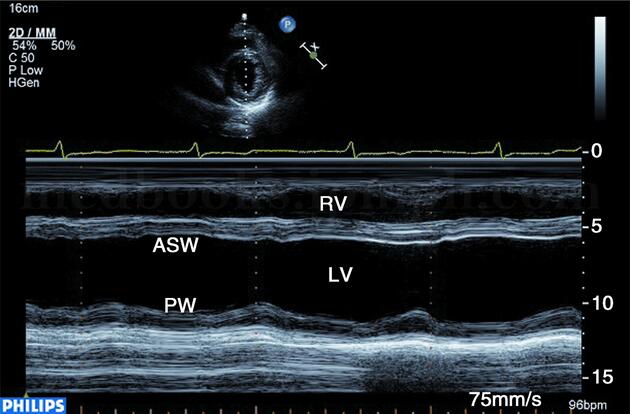

超声图片 如图2‐1‐148。

图2‐1‐148 M型超声示左室前间壁无变薄,运动减弱,后壁运动良好

超声描述 左室各壁心肌未见节段性变薄,前间壁、前壁的中间段和心尖段向心运动减弱且不协调,其余室壁向心运动良好。左室内径正常范围。左室壁未见限局扩张,左室EF57%。

超声诊断 左室前间壁、前壁节段性运动减低,左室收缩功能正常。

临床诊断 冠心病,不稳定型心绞痛,心功能Ⅰ级。